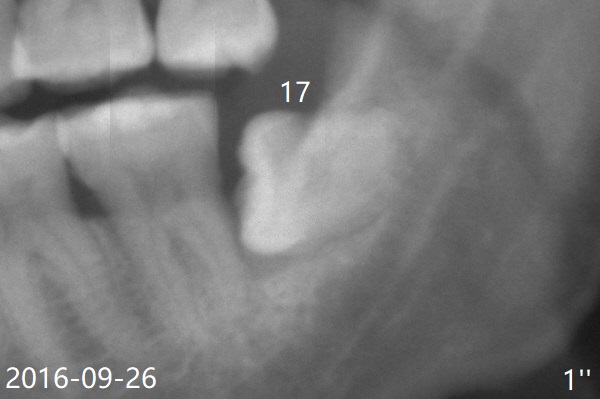

A 51-year-old man returns for #17 extraction 3.5 years post #32 one (Fig.1,2).  The bone distal to #18 is lost severely (Fig.1).